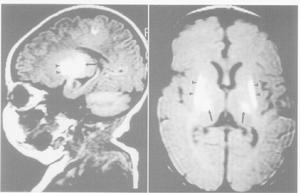

(3)其它:如動態觀察前囪及頭圍的變化,顱透照、頭顱B超及CT檢查等均可根據需要檢測。CT可精確了解病變類型、部位、出血程度,對預後做出估價,具體分度為:Ⅰ度:腦室管膜下出血;Ⅱ度:腦室出血不伴腦室擴張,以上90%存活;Ⅲ茺:腦室出血伴腦室擴張;Ⅳ充:腦室出血伴腦實質出血,其病死率50%。

腦室結構②原發性蛛網膜下腔出血 原發部位在蛛網膜下腔內不包括硬膜下、腦室內或小腦等部位出血後向蛛網膜下強擴展,此種出血類型在新生兒十分常見尤其是早產兒。SAH與缺氧、酸中毒產傷有關。由於出血原因為缺氧引起毛細血管內血液外滲,而肺靜脈破裂故大多數出血量少,無臨床症狀,預後良好部分典型病例表現為生後第2天抽搐,但發作間歇表現正常,極少數病例大量出血常於短期內死亡主要的後遺症為交通性或阻塞性腦積水。

新生兒顱內出血模式圖④膜下出血 是產傷性顱內出血最常見的類型多見於足月巨大兒,近年來由於產科技術提高,其發生率已明顯下降出血量少者可無症狀,出血明顯者一般在出生 24小時候出現驚厥,偏癱和斜視等神經系統症狀。嚴重的天幕、大腦鐮刀撕裂和大腦便淺靜脈破裂可在出生後數小時內死亡也有在新生兒期症狀不明顯,而至數月後發生慢性硬腦膜下積液。